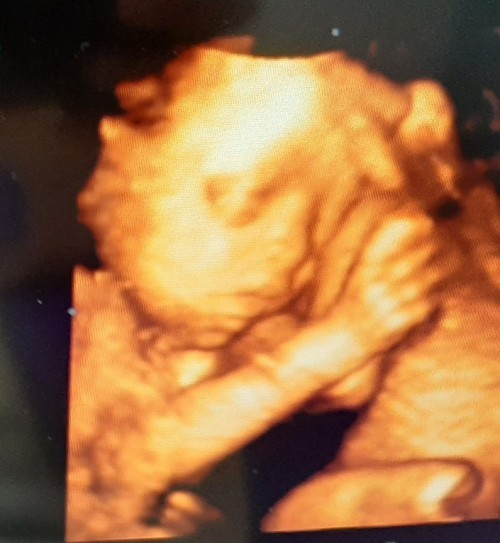

ซาวด์ 4 มิติ ตอน19 W 6Dค่ะ ล่าสุดเมื่อ2วันที่ผ่านมาค่ะ หมอบอกได้ลูกสาวค่ะ